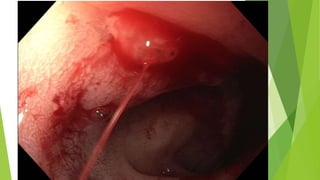

Colonoscopy: diagnostic modality of choice for suspected symptomatic diverticulosis

Findings: well-defined outpouching from the colonic wall

Colonoscopy:is the diagnostic modality of choice for symptomatic

diverticulosis